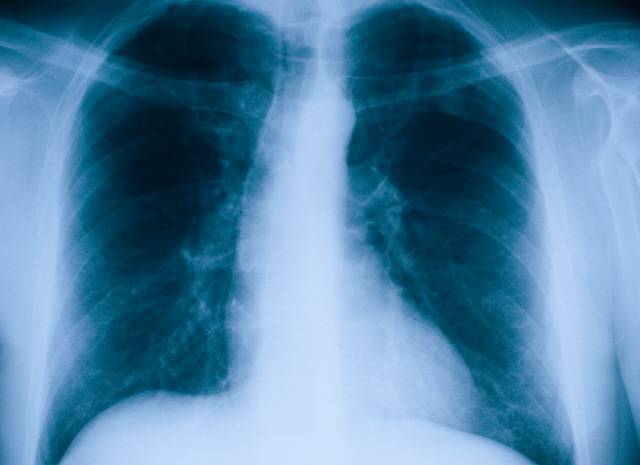

폐렴은 폐에 염증이 생긴 상태를 말한다. 주된 원인은 폐렴구균과 같은 세균이다. 증상은 발열, 오한, 기침 등 감기와 비슷하지만 염증으로 폐에 물이 차면서 고열과 가래를 동반한다. 폐를 둘러싸고 있는 흉막까지 염증이 침범하면 숨 쉴 때 통증을 느끼고 숨이 차게 된다. 건강한 성인은 폐렴에 걸리더라도 별다른 이상을 일으키지 않는 경우도 있다. 경증인 경우 항생제 치료와 휴식만으로도 쉽게 치료가 가능하다.

하지만 65세 이상의 고령이거나 만성질환을 앓고 있다면 얘기가 달라진다. 심할 경우 사망으로 이어질 수 있다. 중증으로 발전할 가능성도 높다. 국내에서 폐렴에 의한 사망자 중 90% 정도가 65세 이상 고령자로 알려질 정도다. 또 고위험군인 임산부나 노인·소아의 경우 폐렴에 걸리면 절반 이상은 입원 치료를 받는다.